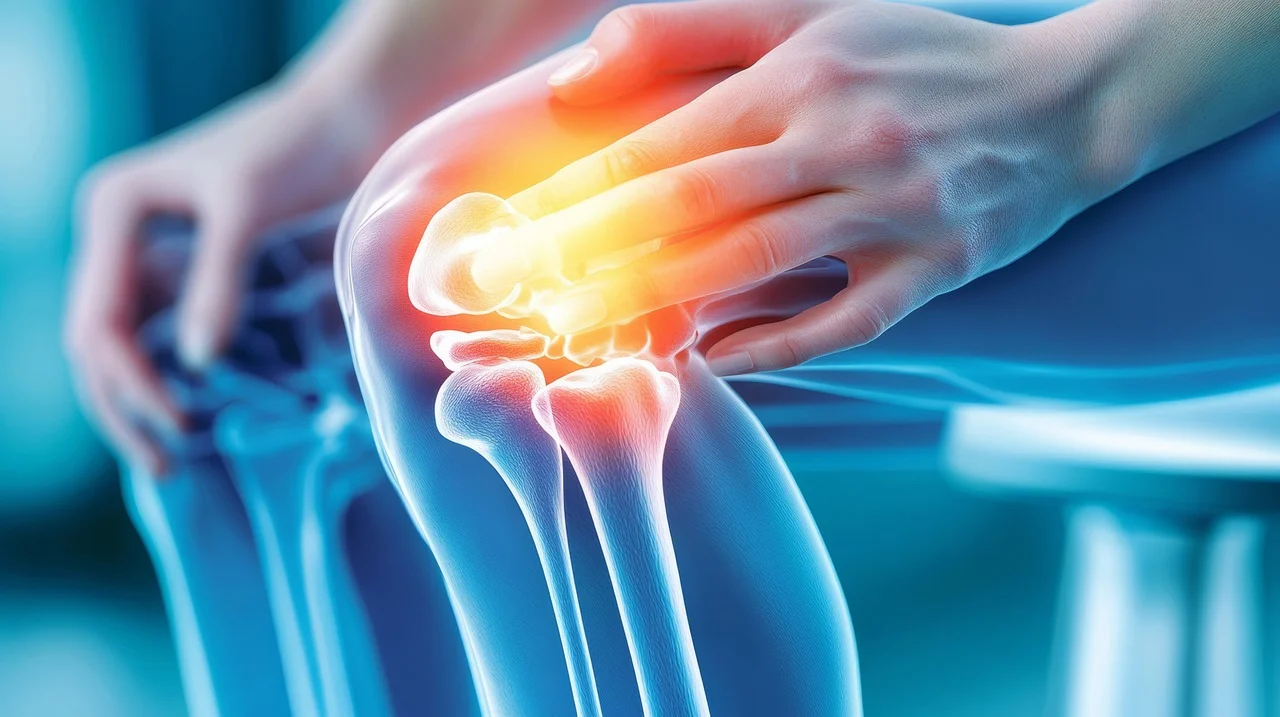

아침에 일어날 때마다 무릎이 뻣뻣하고 쑤시나요? 계단을 오르내릴 때마다 느껴지는 불편함 때문에 활동이 줄어들고 삶의 질이 떨어지셨나요? 나이가 들거나 과도한 활동으로 인해 우리 몸의 연골은 점차 닳아 없어지기 쉽습니다. 연골이 손상되면 관절 통증과 염증이 발생하여 일상생활에 큰 불편함을 초래하죠. 하지만 걱정하지 마세요. 손상된 연골 건강을 관리하고 관절 통증을 줄이는 데 도움을 줄 수 있는 성분이 있습니다. 바로 글루코사민입니다.

연골은 관절에서 뼈와 뼈가 직접 부딪히는 것을 막아주고, 충격을 흡수하며, 부드러운 움직임을 가능하게 하는 쿠션 역할을 합니다. 이 연골은 콘드로이틴과 함께 글루코사민을 통해 건강하게 유지될 수 있어요. 하지만 나이가 들거나, 과체중, 과도한 운동 등으로 인해 연골이 손상되거나 글루코사민 생성 능력이 떨어지면 연골이 닳아 없어지고 탄력을 잃게 됩니다. 이는 결국 관절 통증과 염증을 유발하는 퇴행성 관절염으로 이어질 수 있어요.